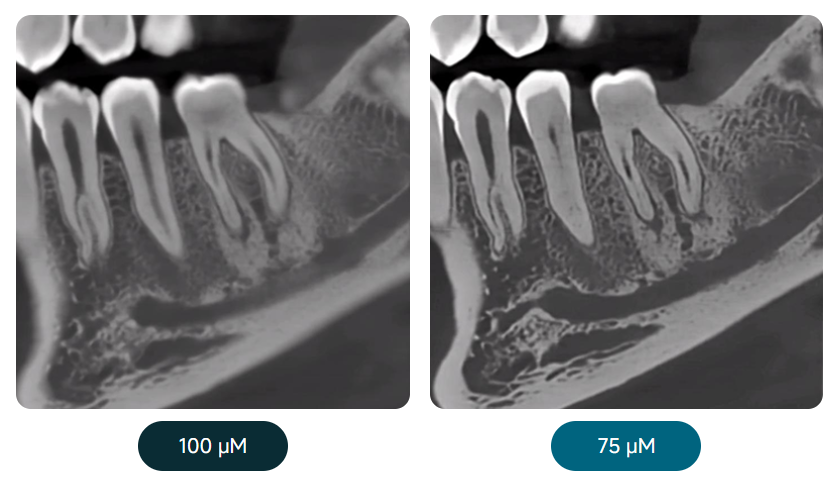

QUALITÉ DE L’IMAGE PREMIUM

Une taille de voxel de 75 μm permet de capturer des détails plus fins.